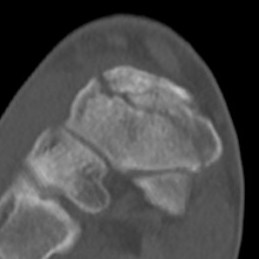

CT

Minimally displaced navicular stress fracture

Displaced navicular stress fracture